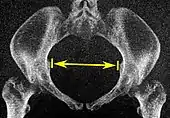

| Pelvic inlet | Transverse diameter of the pelvic inlet | ![]() |

The iliopectineal lines, at widest transverse distance. | 13 to 14.5 cm.[4] |